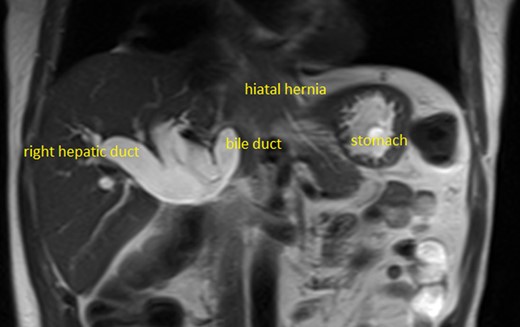

The bilirubin was 158 µmol per litre and the alkaline phosphatase 751 IU/l, gamma glutamyl transferase (GGT) 1560 IU/l, aspartate aminotransferase 110 IU/l, and there was a normocytic anaemia (haemoglobin 130 3G/L). Computed tomography (CT) scan showed a massive hiatus hernia (MHH) containing duodenum and pancreas, and intra- and extra-hepatic biliary dilatation. The bile duct was not obtained at endoscopic retrograde cholangiopancreatography (ERCP), and the ampulla was normal. Magnetic resonance cholangiopancreatography (MRCP) showed a dilated biliary tree with axis deviation of the common bile duct (CBD) causing obstruction and kinking and proximal dilatation, where it entered the hiatal opening (Fig. 1).

This case illustrates an unusual cause of jaundice and the feasibility of repair by laparoscopy even when the pancreas is present in the chest [4]. Diagnosis was greatly facilitated by magnetic resonance imaging (MRI)/MRCP, and ERCP was technically difficult due to the position of the duodenum. The relationship between the hiatus, hernia and bile duct was well visualised confirming clinical suspicion. Occasional reports are present in the literature of pancreatic herniation causing jaundice in MHH [5–7].